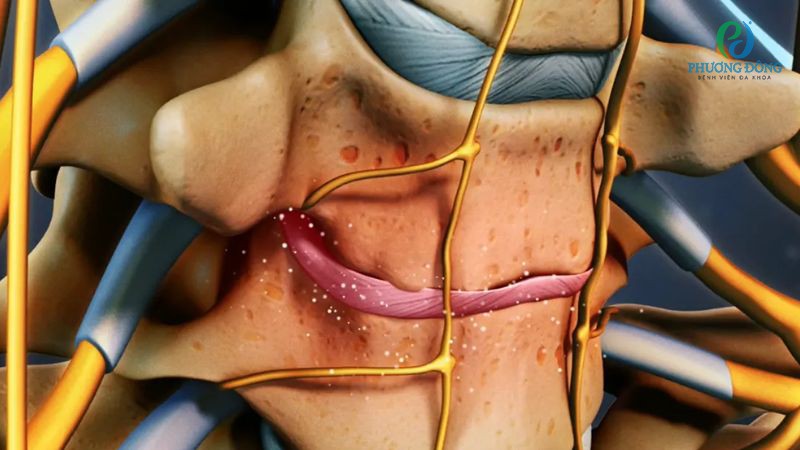

- Thoát vị đĩa đệm: Các tổn thương xảy ra ở lớp vỏ ngoài đĩa đệm, dễ khiến phần nhân mềm bên trong tràn ra ngoài. Nếu nghiêm trọng hơn, tình trạng này có thể chèn ép lên tủy sống hoặc rễ thần kinh.

- Gai xương: Thông thường khi đĩa đệm bị thoái hóa, cơ thể có xu hướng tạo thêm xương như một phản ứng tự nhiên, nhằm mục đích củng cố cột sống. Song, sự hình thành quá mức của gai xương sẽ gây áp lực lên tủy sống cũng nhưu rễ thần kinh.